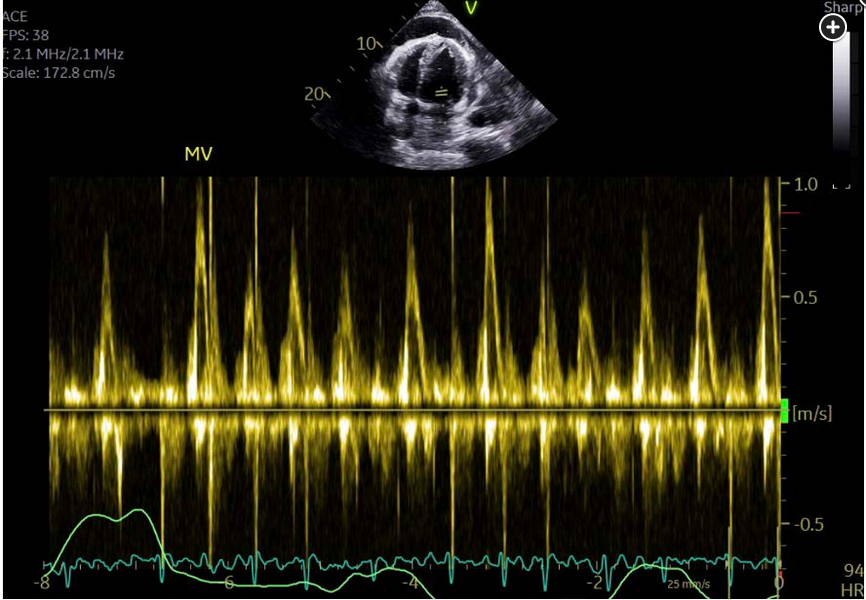

Still images of the echocardiogram show a four-chamber view demonstrating a large anterior pericardial effusion (Figure 1) and significant respirophasic variation of mitral valve inflow (Figure 2). The variation in mitral (and tricuspid) inflow with respiration has the same mechanism as pulsus paradoxus.

Mitral inflow velocity variation greater than 25% and tricuspid inflow velocity variation greater than 40% are considered significant and thus indicate a hemodynamically significant effusion. RV collapse in diastole is the echocardiographic hallmark of frank tamponade.12